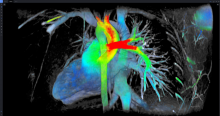

Radiation Oncology | December 12, 2023

Imaging advancements, including 3D Doppler imaging to detect cancers in numerous organs, are used to accurately guide biopsies, target therapy and provide focused follow-up after treatment. ITN spoke with current editorial advisory board member Robert L. Bard, MD, PC, DABR, FASLMS, to find out more about recent advancements in diagnostic radiology. This video is Part 1 of a 3-part video series.

Dr. Bard is internationally known and recognized as a leader in his field. He specializes in advanced 3-D Doppler imaging to detect cancers in numerous organs, including the breast, prostate, and other areas. His images are used to accurately guide biopsies, target therapy and provide focused follow-up after treatment. He is committed to improving non-invasive cancer testing and developing minimally invasive image guided technologies to prevent cancer spread.